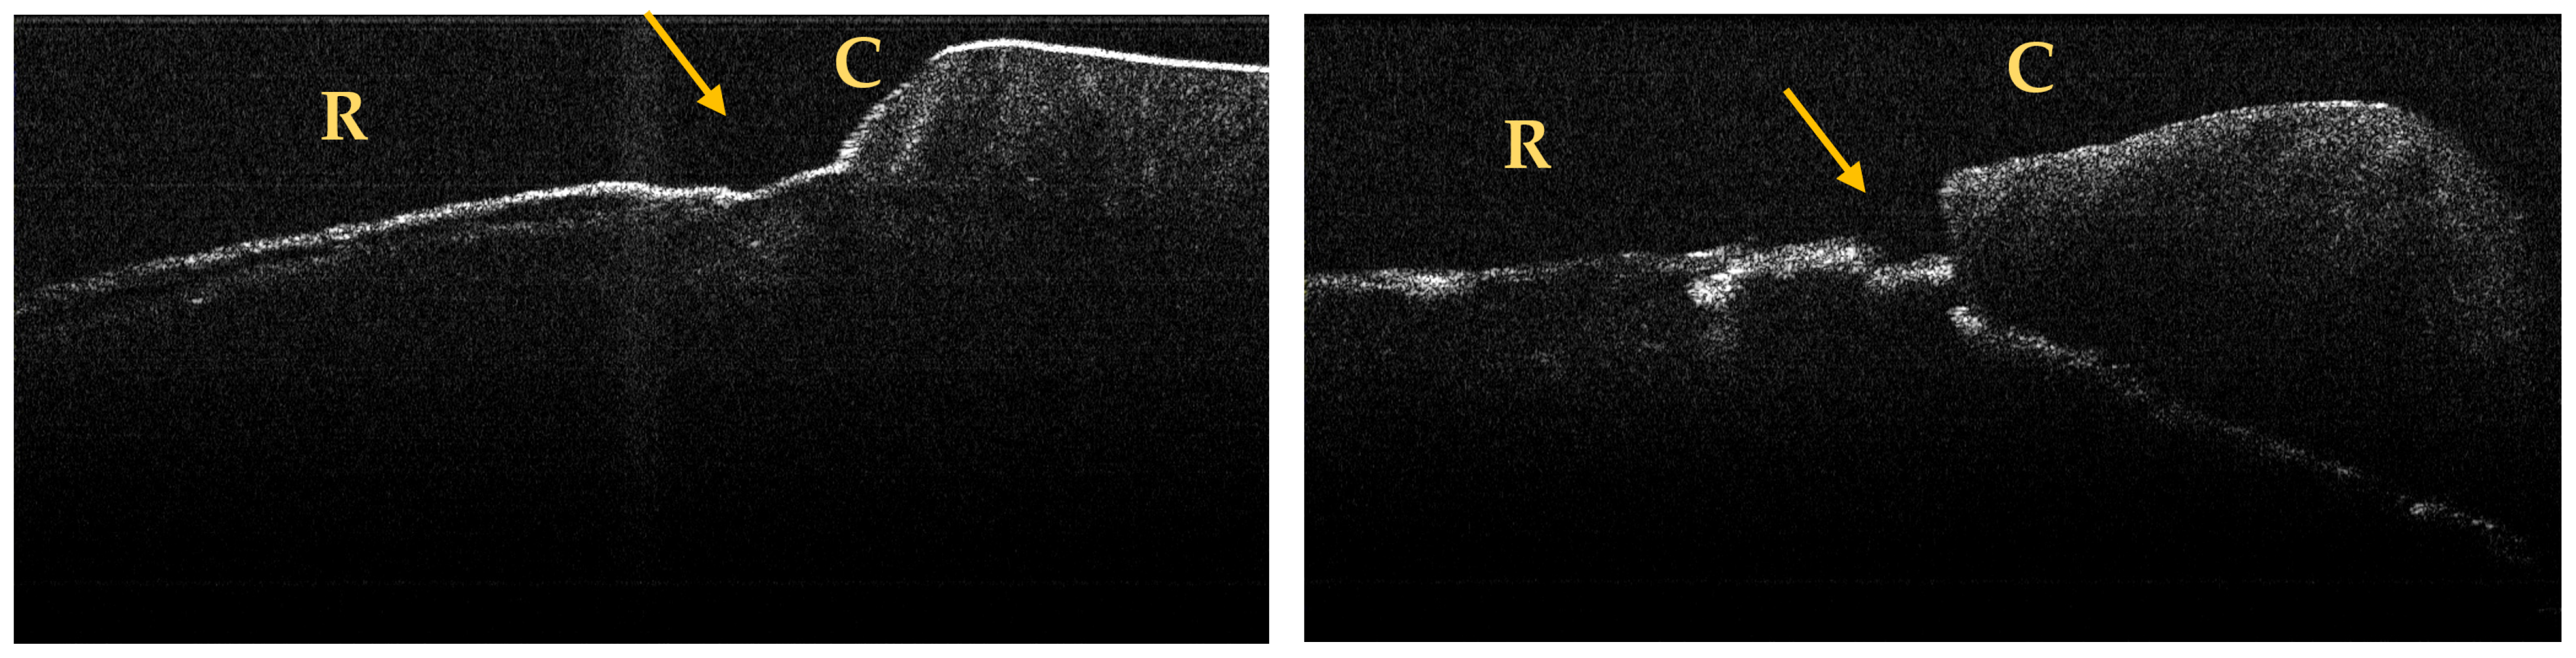

3.2. OCT Examination of Teeth Included in the Study